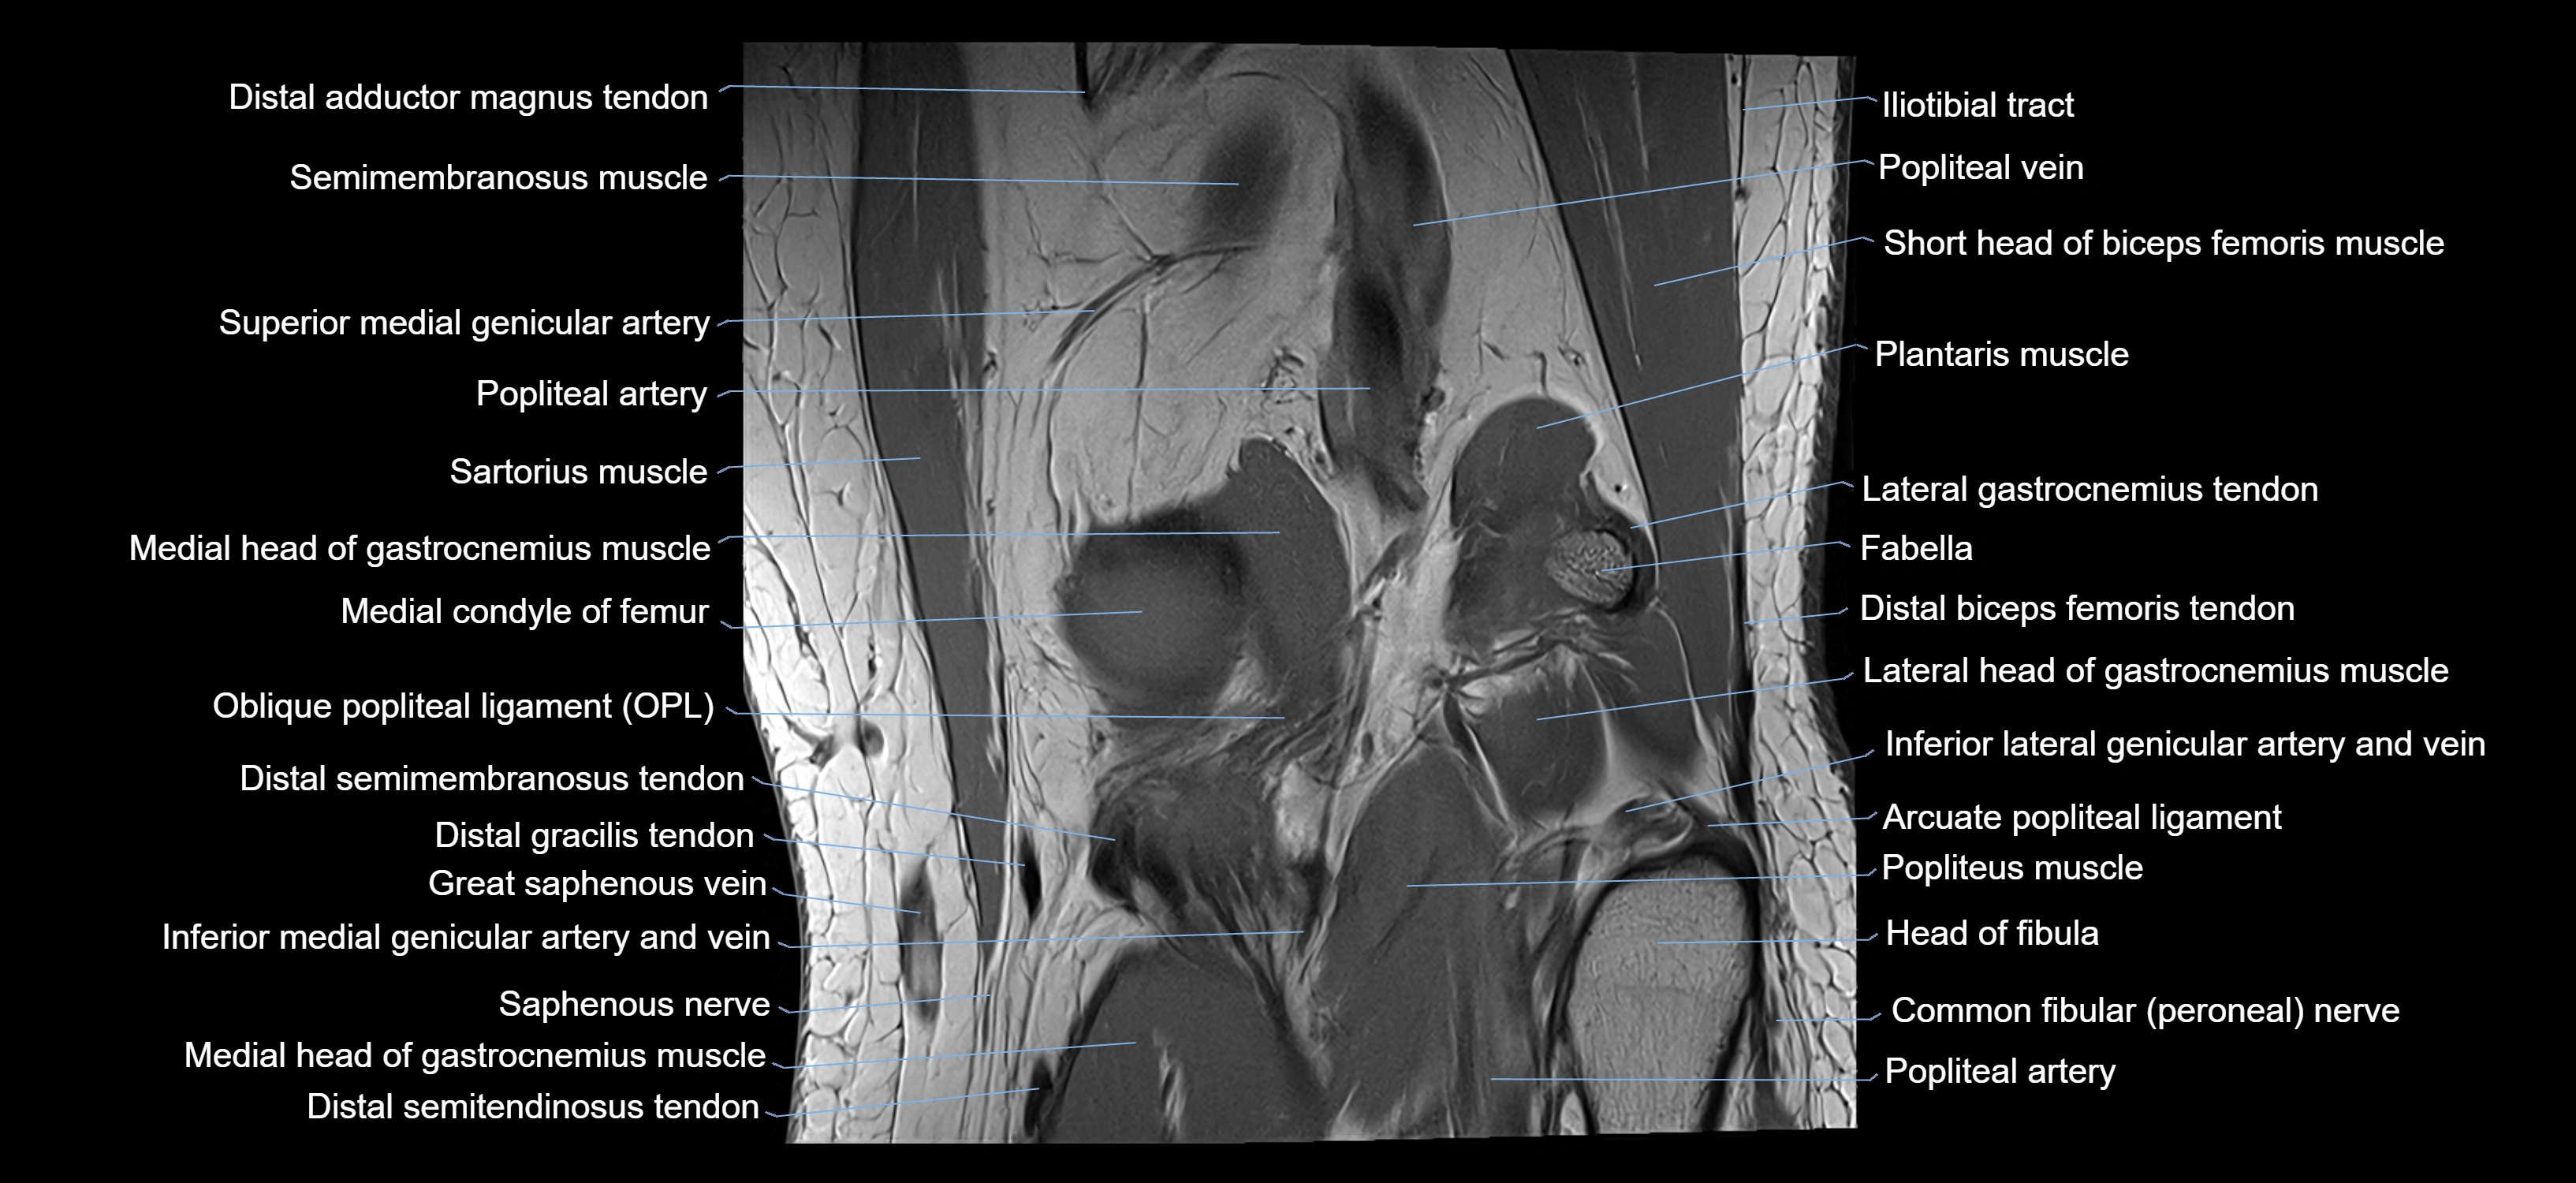

- Arcuate popliteal ligament

- Distal adductor magnus tendon

- Distal biceps femoris tendon

- Distal semimembranosus tendon

- Distal semitendinosus tendon

- Gracilis tendon (Distal)

- Head of fibula

- Lateral gastrocnemius tendon

- Lateral head of gastrocnemius muscle

- Medial gastrocnemius tendon

- Medial head of gastrocnemius muscle

- Oblique popliteal ligament

- Popliteal artery

- Popliteal vein

- Popliteus muscle

- Sartorius muscle

- Semimembranosus muscle

- Semitendinosus muscle

- Superior lateral genicular artery

- Superior medial genicular artery